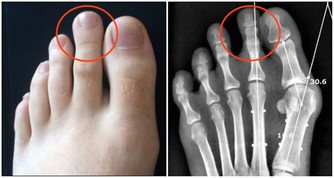

第四個信號:更容易傳染疾病,傷口更難癒合免疫力降低,我們的身體也就更容易被疾病傳染,同時清除外來病菌的能力也會更弱。

所以這就會導致傷口需要更久的時間癒合,一些皮膚疾病也更難根治。

如灰指甲和甲溝炎等皮膚疾病反反覆復,就有受到身體的免疫力降低的影響因素。

註:濕疹和蕁麻疹的爆發也和身體的免疫力變化有關。